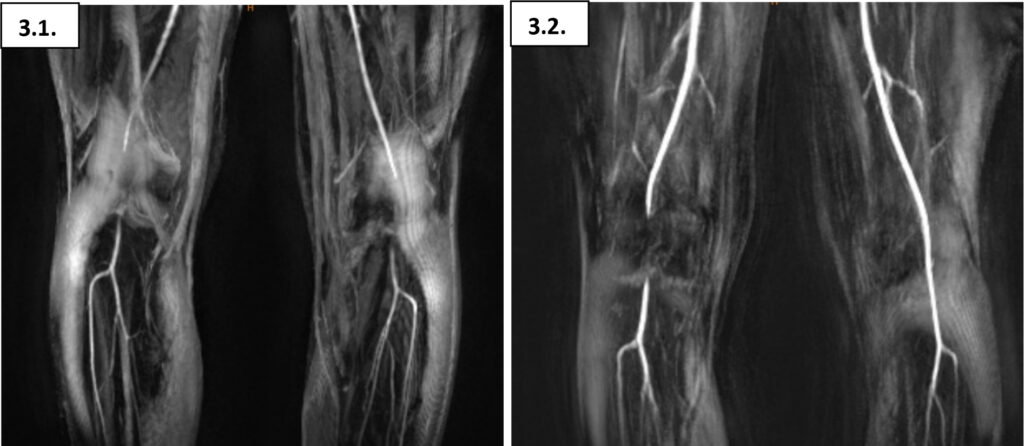

25-jährige Fußballerin mit belastungsinduzierten drückenden und krampfartigen Wadenschmerzen beidseits (linksbetont, Crescendo und Decrescendo des Schmerzes innerhalb von Sekunden) nach Laufstrecken von 2 ½ km. In der Vergangenheit wurde ein Logensyndrom der tiefen Wadenflexoren diagnostiziert und endoskopisch-assistiert gespalten. Dies, sowie rezidivierende intramuskuläre Botulinumtoxin-Injektionen in die Wadenmuskulatur haben keine anhaltende Beschwerdelinderung herbeiführen können.

Im Gegensatz zum belastungsinduzierten chronischen Kompartmentsyndrom zeigt sich beim Entrapment-Syndrom der Arteria poplitea eine belastungslimitierende Schmerzentwicklung innerhalb weniger Sekunden, welche sich nach Sistierung der Belastung auch ebenso schnell wieder verflüchtigt. Dementsprechend ist die Demaskierung eines Kompressionssyndroms der Arteria poplitea mittels Knöchel-Arm-Index nach Laufbandbelastung oft schwierig, bzw. nicht selten falsch-negativ. Eine Duplexsonographie der Kniekehlenarterie in Bauchlage unter entsprechender Provokation in Plantarflexion kann hierbei meist zielführend sein. Eine anschließende CT-/MR-Angiographie (ebenfalls unter Provokation) dient dem behandelnden Gefäßchirurgen dann zur besseren Visualisierung der Anatomie im Bereich der Fossa poplitea. Am häufigsten zeigt sich hierbei eine Kompression der Arteria poplitea durch den medialen Musculus gastrocnemius.

Die Inzidenz eines poplitealen Entrapments mit anatomischem Korrelat in der Fossa poplitea befindet sich bei rund 0,6 – 3,5 %. Nicht selten findet sich duplexsonographisch jedoch eine Kompression der Kniekehlenarterie im Bereich der Soleus-Schlinge ohne eigentliche anatomische Variationen, was als funktionelles Entrampent definiert wird und primär konservativ behandelt werden sollte. Liegt hingegen eine anatomische Anomalie vor ist die offen-chirurgische Dekompression mi-t Myektomie (meist des medialen Musculus gastrocnemius) die Therapie der Wahl [5].